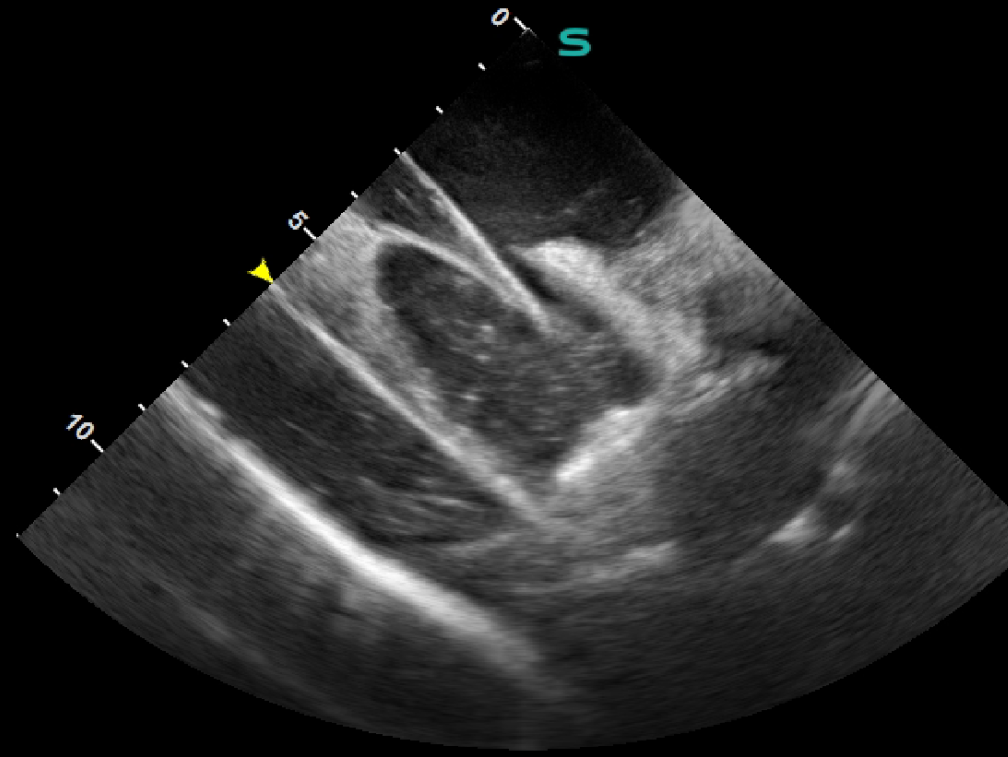

ICE导管经股静脉入路输送至患者的右心房,通过导管调弯,可以清晰观察到右心房、右心室、三尖瓣、房间隔、左心房、左心耳、左心室、二尖瓣等心脏结构,并通过超声心动图完成了血流的评估和卵圆孔未闭的评估。在ICE的指导下,封堵器一气呵成地完成释放。术后实时的超声心动图显示封堵器位置固定完美,封堵效果理想,手术取得圆满成功。ICE系统的超声影像质量和导管操控性能均表现优异,获得了临床专家的一致好评。

影像图片

封堵前的ICE评估确认

ICE指导PFO封堵